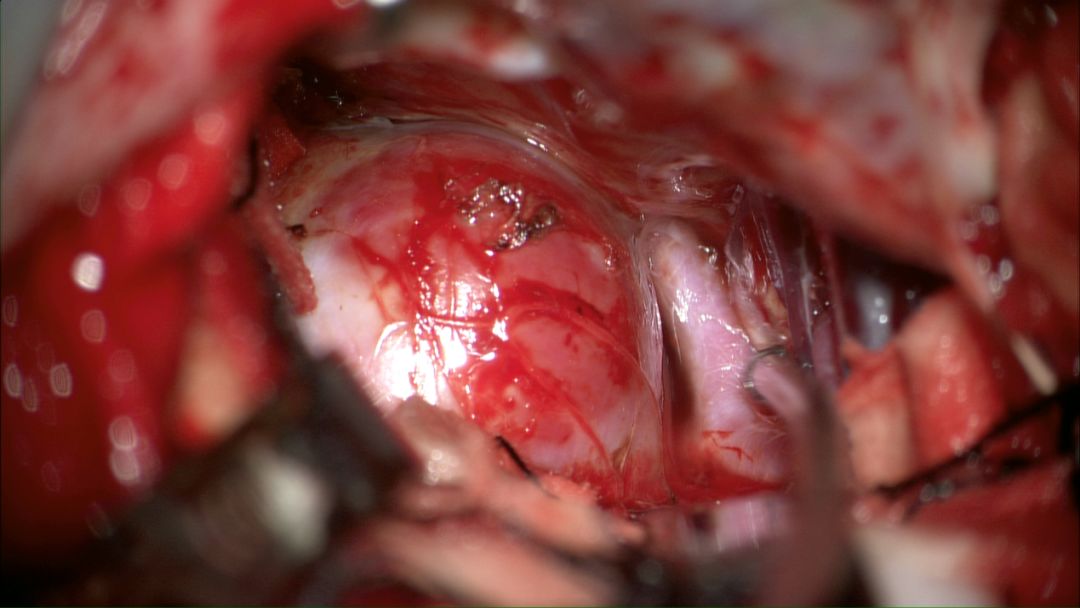

2018.5.8患者全麻下行临时球囊阻断下右侧眼动脉大动脉瘤夹闭术。术中取右侧额外侧入路,形成骨瓣约4*4cm大小,牵开额底,切开蛛网膜释放脑脊液后即见动脉瘤。术中所见瘤体与周边结构解剖关系和术前融合图像完全一致。瘤体表面张力较高,牵开瘤体困难,无法暴露瘤颈和近心端动脉。

术中动脉瘤所见

再次探查动脉瘤发现瘤体表面张力明显下降,探针分离瘤颈,以2枚直动脉瘤夹792+760夹闭瘤颈。解除球囊阻断后,动脉瘤表面张力无回升,穿刺瘤体无活动性出血。荧光造影提示瘤体无显影,载瘤动脉血流通畅,无明显狭窄,各分支保留完好。切除部分瘤体,视神经减压。DSA复查提示动脉瘤夹闭满意,全脑血管通畅后关颅。(球囊阻断时间约10分钟)

术中夹闭情况